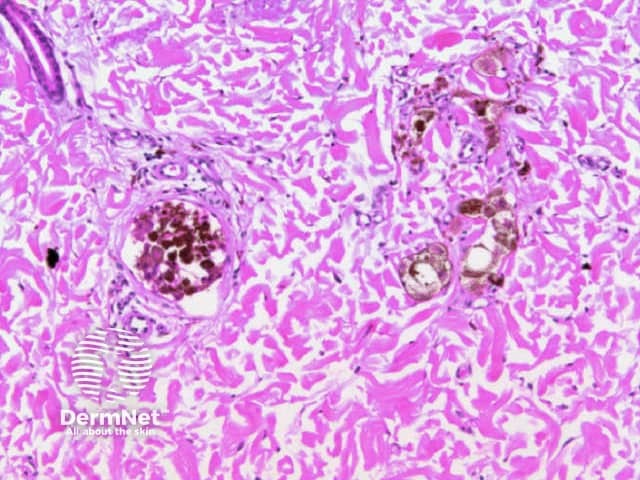

Dots are small enough to have no discernable shape at the magnification provided by a dermatoscope. They represent melanin, or occasionally haemosiderin, with the colour depending on the level of the pigment within the skin in the case of melanin. Dots may be black (superficial epidermal melanin), brown (basal epidermal melanin or superficial dermal haemosiderin), grey (papillary dermal melanin) or blue (reticular dermal melanin). They are usually present in association with another pattern. Brown or grey dots are occasionally found without another pattern (Figures 34-36). Red dots, representing a vascular pattern, are discussed later.

Black dots result either from pagetoid pigmented melanocytes or free pigment within the stratum corneum. Brown dots reflect either small nests of melanocytes in the basal epidermis, focal pigmented keratinocytic proliferation, as seen in some forearm solar lentigines, or superficial dermal haemosiderin deposition. Grey dots are due to melanin pigment within the papillary dermis, either free, in small nests of melanocytes or, more commonly, in melanophages. Blue dots reprresent deeper dermal melanin. The differential diagnosis of dots on dermatoscopy is shown in Figure 34.